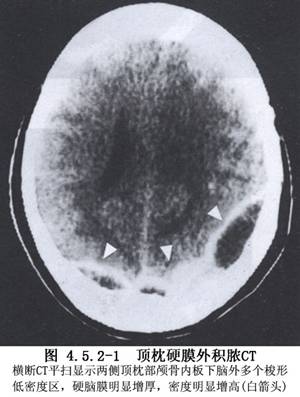

继发于颅骨骨髓炎的硬脑膜外脓肿,在充分显露出病骨时,随即在病变颅骨上钻孔,并以咬骨钳咬除病骨,将视野下的硬脑膜外脓液、炎性肉芽组织、死骨与异物一并清除。若无颅骨骨髓炎的病人,在已经确定脓肿部位的颅骨上钻孔,穿刺以证实脓肿存在。

4.清除脓液和硬脑膜外炎性肉芽组织,根据炎性病变的范围扩大颅骨切除,直到病变周围均显露出正常的硬脑膜(图4.5.2-2),术后才能顺利愈合。